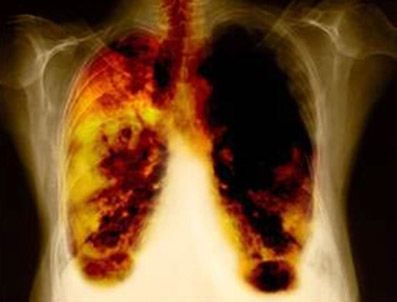

SAĞLIK